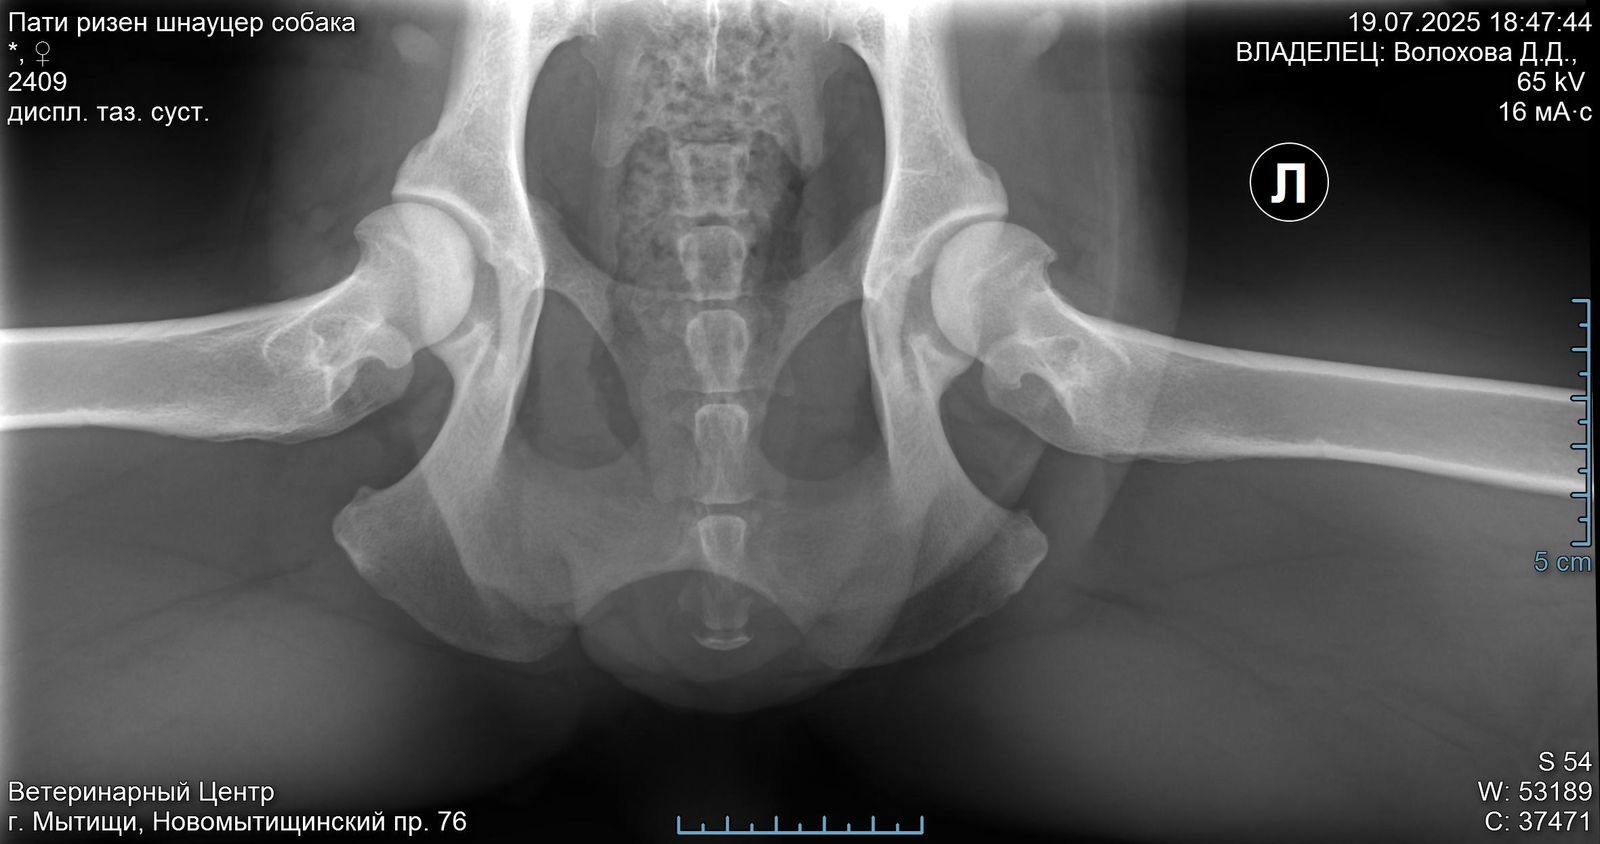

Лапа

Задние ноги не идеал, но портить жизнь не должны.